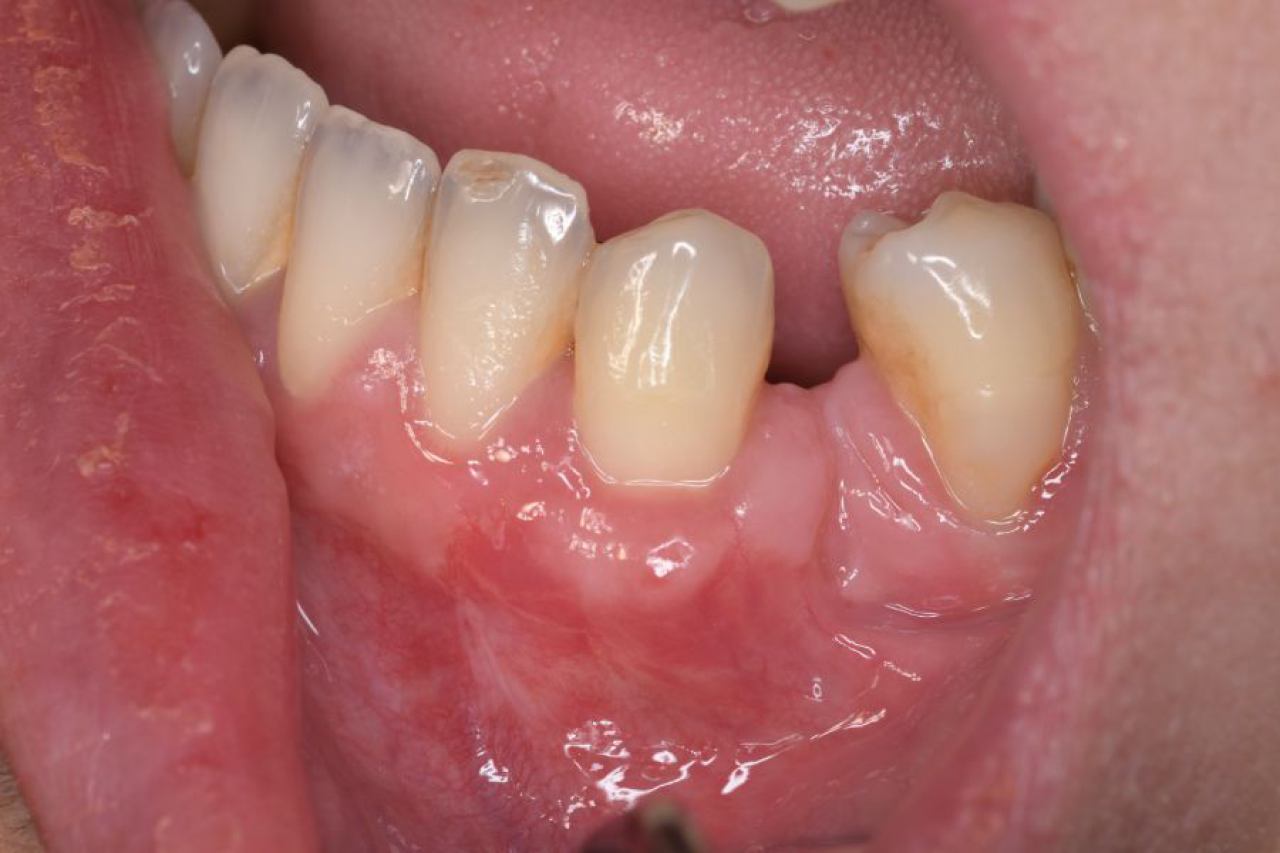

Regeneracija kosti i mekog tkiva

Gingivalne recesije u narodu poznatije kao „povlačenje zubnog mesa" moguće je korigirati kirurškim zahvatom te vratiti gingivu (zubno meso) u fiziološki položaj mikrokirurškim tehnikama. Zahvati koje odrađujemo kod regeneracije kosti i mekog tkiva su podizanje dna sinusa (sinus lift) i nadomještanje izgubljenog volumena kosti (augmentacija kosti, regeneracija kosti).

Implantologija - ugradnja dentalnih implantata

Dentalna implantologija je grana dentalne medicine koja objedinjuje znanje iz kirurgije, parodontologije i protetike i bavi se ugradnjom implantata u bezubu kost gornje ili donje čeljusti.